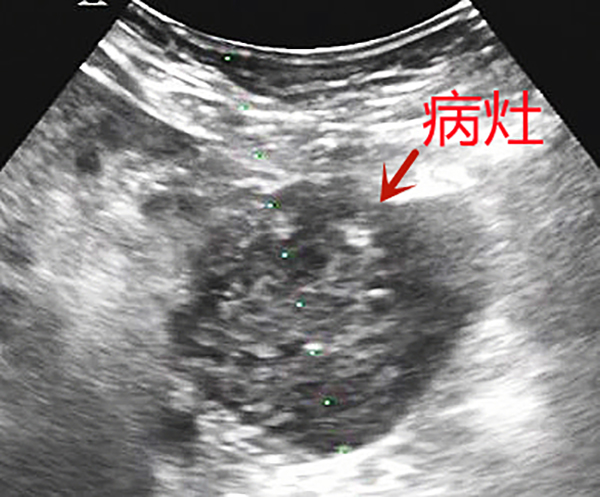

55歲的曹大叔咳嗽、咳痰3個多月了,在外院做增強CT提示胰腺占位性病變,為求進一步診治,他來到我院腫瘤科就診。為了制定合適的治療方案,腫瘤科三病區(qū)主任陳日新和主治醫(yī)師王磊黎、石周綜合評估后,建議實施超聲引導下經(jīng)腹胰腺穿刺活檢術以明確病理診斷。

超聲科張步林主任及張煒副主任在接到腫瘤科的會診請求后,認真分析,根據(jù)胰腺腫瘤位置、大小、壞死范圍,反復評估與周圍重要臟器的解剖關系,權衡相對安全的穿刺路徑,考慮到術中可能因為患者呼吸動度的變化造成穿刺路徑偏移,術前多次跟患者溝通進行憋氣練習,并且計劃利用超聲科的介入法寶——超聲穿刺探頭,通過兩個大血管之間幾毫米的微小間隙進行超聲引導下進針,避免傷到周圍組織及大血管。

一切準備就緒,超聲實時引導下,局麻、進針、精準避開血管、到達腫瘤表面、激發(fā)活檢槍、順利取材、迅速拔出,憑借張步林主任和張煒副主任的實踐經(jīng)驗,整個過程一氣呵成。

術后觀察穿刺區(qū)域未見明顯出血,患者無明顯疼痛及其他并發(fā)癥,整個穿刺活檢過程僅用時不到十分鐘。